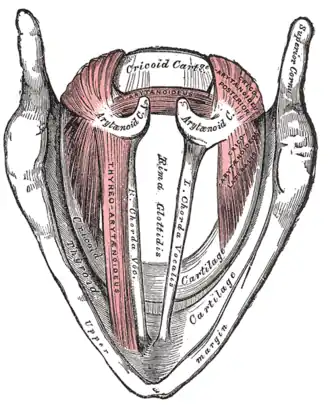

Additional images

Muscles of the larynx, seen from above.

Muscles of the larynx, seen from above.